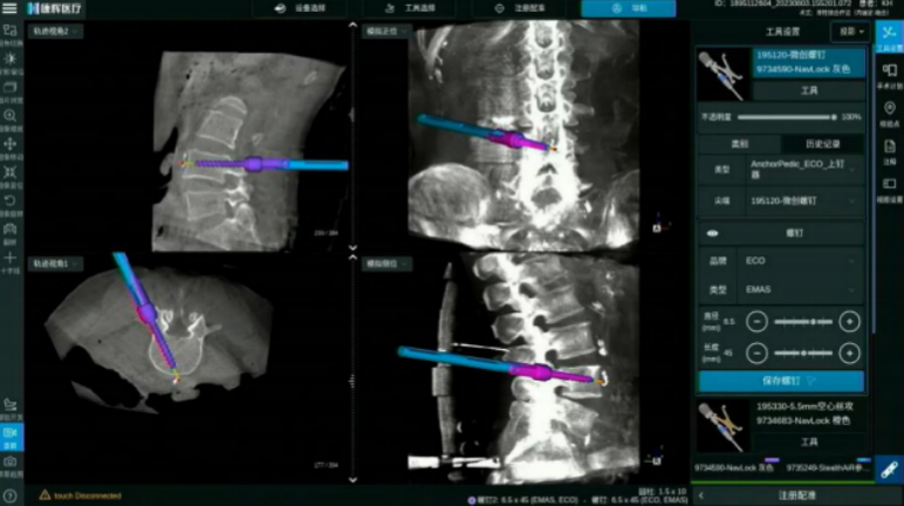

頸椎后路內固定

全程可視化帶來頸椎手術精準性的提升

ECO/Anchor與導航化學連接 螺紋級可視

電動手柄配合導航實現可視化動力置釘

· 無導絲置釘流程, 手術更加精準安全

· 開路、絲攻、置釘,手術全程步步實時可視

· 實時呈現手術工具、 內植入物清晰邊界

· 可拓展至椎間處理步驟 三維實時可視